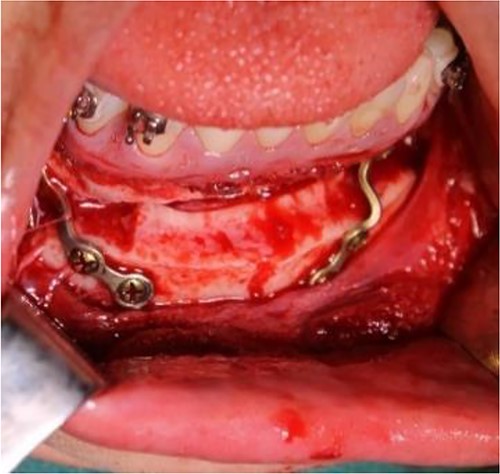

The surgical procedure was performed under general anesthesia (fiber-optic nasal intubation) and consists of two phases: removal of the ankylotic mass and insertion of the temporomandibular joint prosthesis [10]. Alkayat-Bramley and submandibular approaches (Fig. 5) were made bilaterally to gain access to the temporomandibular joint area and the mandibular ramus, respectively. After accessing the temporomandibular joint area, resection of the ankylotic mass and creation of space for the placement of the temporomandibular joint prosthesis were performed bilaterally using cutting guides (Fig. 6) along with a left-sided coronoidectomy. Then, intermaxillary fixation (IMF) was applied. In the initial phase, dummy prostheses were inserted bilaterally to check fit and function, which were eventually replaced by the final custom-made prosthesis. The IMF was then removed, and the patient’s mandible was manipulated to ensure that joint motion was not impeded and that the two prosthetic components fit together properly. Surgical drains were placed bilaterally, and then the surgical sites were closed in layers.

Intraoperative clinical images: positioning and final fixation of the custom prosthesis with screws.